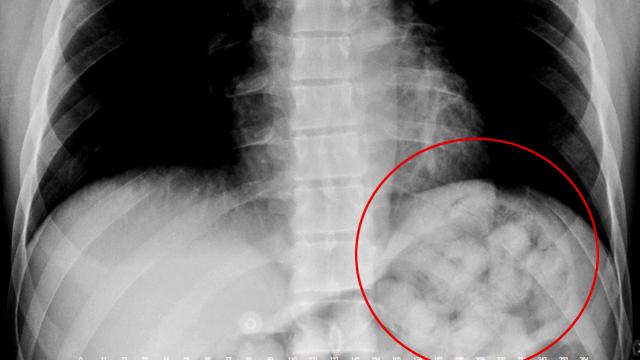

Narziveh’in röntgen filmlerinde midesinde uyuşturucu madde kapsülleri görüldü. Bunun üzerine Narziveh mahkeme kararıyla ameliyata alındı.

Ameliyatın ardından şüphelinin midesinden ikisi patlamış halde 72 kapsül içerisinde yaklaşık 900 gram metamfetamin çıkarıldı.